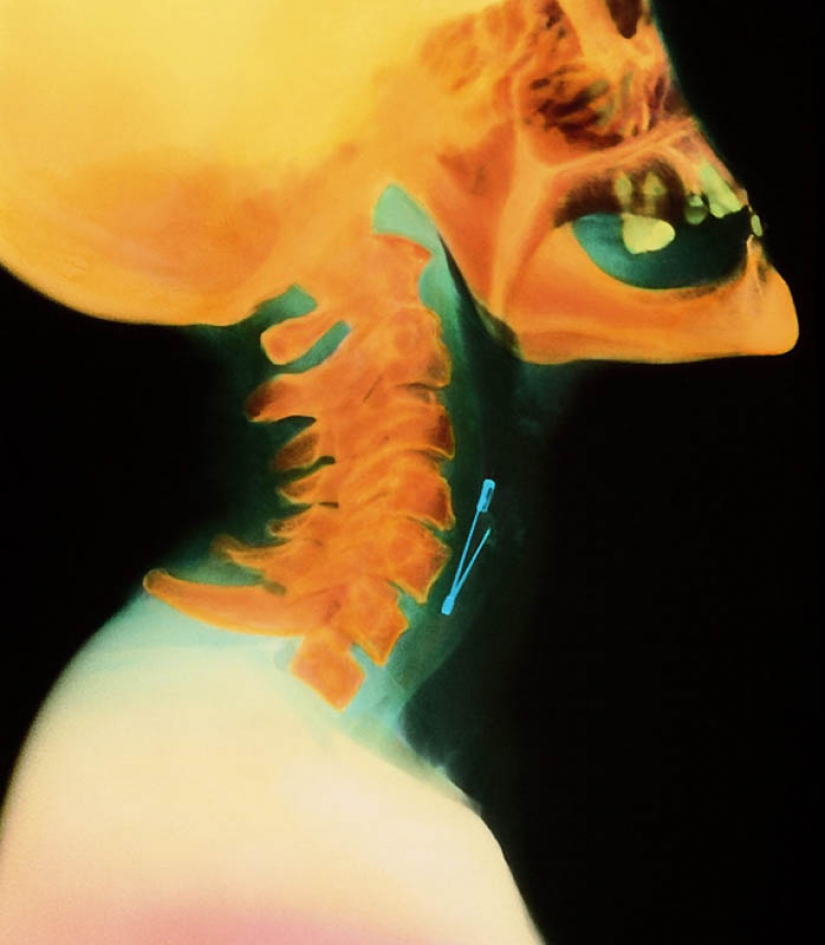

6. El pasador de la mujer de la garganta.